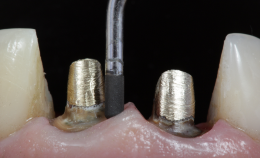

Preparo com CVDentus: Sem danos à membrana pulpo-dentinária. Preservação dos odontoblastos (CO), dentida tubular (DT), pré-dentina (PD) e zona acelular (ZA).